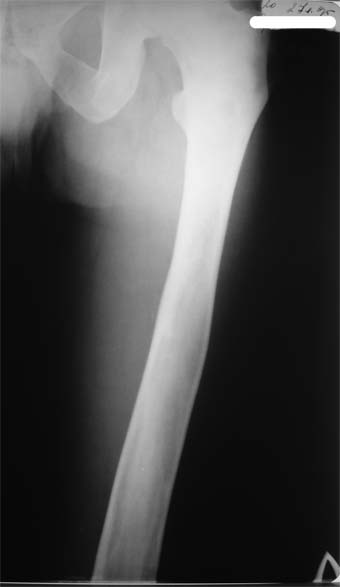

Коллеги!Пациент Д., 35 лет, В 1985 году был поставлен диагноз гемигипоплазия правой нижней конечности. Укорочение 5 см, в 1987 году остеотомия правого бедра, аппарат 4 месяца, удлинили на 2 см из-за нагноения спиц аппарат сняли. В настоящее время Жалобы на дискомфорт, тяжесть в левом бедре, голени при длительной ходьбе, при длительном лежании на левом бедре. Эти жалобы беспокоят втечение 5-6 лет. В 1999 году выявили "изменения" (со слов больного, выписки нет на руках) бедренной кости и костей голени слева. Тогда же предложили в ЦИТО срочно делать какую-то операцию. При осмотре: Правая нижняя конечность. Имеются рубцы на правом бедре по наружной и внутренней поверхностям. Ограничения движений в коленном суставе нет. Кровоснабжение, иннервация сохранены. Левая нижняя конечность. Левое бедро увеличено в объеме, при пальпации пальпируется бедренная кость большего диаметра по сравнению с левым бедром. Пальпация безболезненна. Голень обычной формы. Объем движений в суставах полный. Кровоснабжение, иннервация сохранены. Имеется разница в длине конечностей правая короче на 4-5 см за счет бедра и голени. В приложении вид больного и рентгенограммы бедра 2001 год и 2005 год. Что бы это могло быть? О чем можно думать? Онкология? С уважением Коробушкин Глеб Владимирович Российский государственный медицинский университет кафедра травматологии, ортопедии и ВПХ, доцент

Остеосклеротическая стадия болезни Педжета. Имею двух подобных больных по 15 -20 лет наблюдения. В острой стадии - текли как классическая саркома. "За" - все (рентген+биопсия+клиника) - отправили хоронить, а в результате живы и имеют рентген-картинку похожую Вашей. Поройтесь в минеральном обмене и в почках. Удлинять подобные кости опасно. Можно -биопсию на всякий случай (из зоны склероза и зоны пороза).

У больного полиоссальноая форма фиброзной дисплазии с поражение левой бедренной и большеберцовой кости. На рентгенограммах - тотальное разрастание и остончение кортикального слоя. Имеется удлинение левой нижней конечности на 2,5-3 см за счет голени. Больному показано оперативное лечение левой большеберцовой кости.